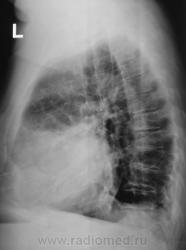

Версия, полагаю терапевтов, о плеврите интерсна. Вопрос другой - что же это за "зверь" в передне-медиальном отделе слева? И еще оболее интересное предположение, а связан ли "он" вообще с левым легким?...а не имеет ли "он" отношения к сердцу?

Решили делать "томо" в боковой проекции.

Честно говоря, никогда со столь необычной локализацией и формой осумкованого  плеврита не встречался...а в голове все время вертится неотвязная мысль "миксома????"...хотя это далеко не факт...

Валентин Львович, а ведь никто не сказал, что и слева не может быть целомических кист перикарда, в т.ч. и таких больших?

Я думаю, многие вопросы может снять R-скопия лёгких. Странно, что при столь выраженных изменинеиях нет особой клиники...Скорее, изменения связаны с сердцем или перикардом, возможно какое-то доброкачественное образование(?).